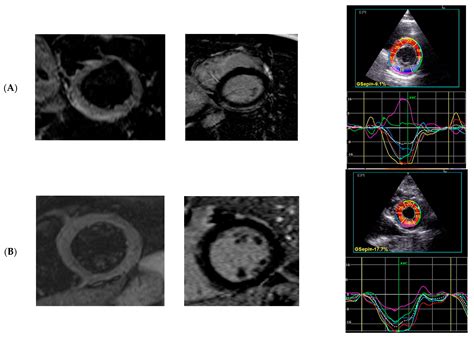

2D Strain Analysis in Myocarditis—Can We Be Any Closer to Diagnose the ...

mdpi.com